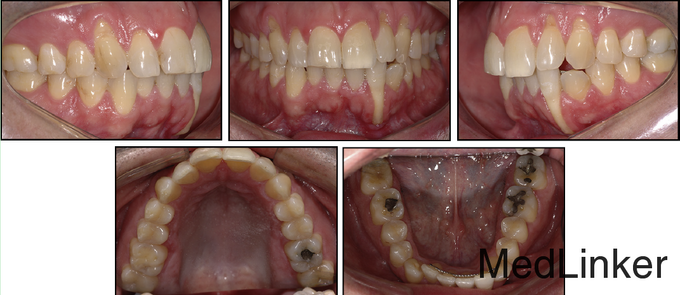

36岁,男性,主诉下颌左侧侧切牙唇侧牙龈退缩明显,伴有疼、刺激痛症状。 骨性牙性II类已经在几年前于外院矫治完成,,上颌佩戴可摘保持器,下颌3-3舌侧丝粘接保持

舌侧丝保持器在右侧侧切牙与尖牙间被破坏,右侧中切牙与侧切牙舌向移动,而左侧尖牙唇向移动。下颌运动过程中,左下2承受了切导的全部负荷。左下2活力测试显示无活力。CT矢状向显示32牙完全位于骨皮质外,32牙根尖1/3横断面显示牙根周围无骨质包绕